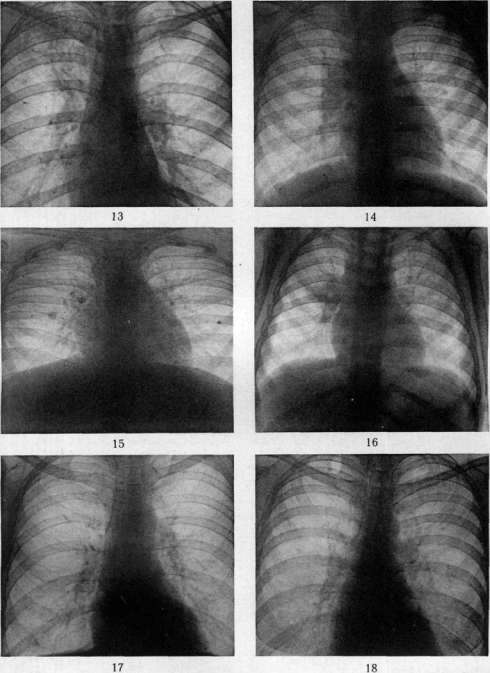

гематогенной генерализацией в результате проникания туб. бацил в ток крови непосредственно или через посредство лимфы (см. Туберкулез). В легких гематогенное поражение проявляется разно. При обшем милиарном Т. в обоих легких наблюдается высыпь массы милиарных туберкулов [см. отд. табл. (ст. 119—120), рис. 3]; в этих случаях ткань легких представляется полнокровной и на таком фоне видны бугорки в зависимости от возраста и типа их или мелкие, серые, полупрозрачные или желтые, с неровными контурами, часто более крупные. Нередко можно, согласно указанию Рибберта (1902), заметить, что у взрослых в верхних районах легких бугорки несколько более крупны, чем в нижних, что объясняют более энергичным ростом туберкулов именно в верхних отделах легких. Если проникание туб. бацил произошло в ветвь легочной артерии, то мидиариза-ция захватывает лишь соответствующую часть легочной территории. Микроскоп, исследование при милиаризации в легких может открыть разный тип бугорков: иногда это типичные продуктивные эпителиоидные бугорки, имеющие своим источником развития альвеолярные перегородки; бугорки растут, сдавливая и уничтожая альвеолы и оставаясь долго продуктивными бугорками; в других случаях к бугорку, начавшему развиваться в альвеолярной перегородке, быстро присоединяется эксудация в альвеолы; наконец бывает так, что бугорок как бы сразу возникает в виде милиарной пневмонии, захватывающей 2—4 соседних альвеолы (милиарный альвеолит), и таким образом обнаруживает экеудативный характер. Гюбшман и Шлейсинг выдвигают ту точку зрения, что всякий бугорок в легких начинается в виде милиарной пневмонии и уже потом окружается продуктивной зоной. Эта точка зрения вызвала категорические возражения крупнейших патологов (Герксгеймер, Ашоф, Штернберг и др.); кроме того Гретман (Grethmann, 1928) установил, что гематогенные милиарные бугорки в легких как правило развиваются в виде продуктивных бугорков из стенок мелких сосудов; эксудация в альвеолы есть явление последовательное, частое, но не обязательное. Гематогенное метастазирование в легкие может еще происходить в виде появления в легких одного или нескольких туб. очагов; по своему существу такая форма есть частное проявление органного T.j возникающего в порядке поздней генерализации первичного Т. (см. Туберкулез). Судьба и выражение таких отдельных гематогенных фокусов в легких бывает разной (см. ниже). Попытка Симона (Simon) объяснить все верхушечные рубцы, встречаемые в легких взрослых, гематогенным метастазированием, происходящим в детстве, у патологов не имела успеха; такое гематогенное метастазирование в верхушку легкого в детском возрасте встречается редко и на детских трупах мы не встречаем ничего похожего на начало образования этих очагов; верхушечные рубцы легких наблюдаются почти только у взрослых, и частота их возрастает с возрастом. Первичный Т. приводит к смерти детей или в связи с значительным распространением туб. процесса в легких или в связи с генерализацией, особенно в виде общего милиарного Т. и туб. менингита, У взрослых первичный Т. легких бывает очень редко; чаще всего это касается тех народностей, к-рые в детском возрасте не соприкасаются с туб. вирусом (см. Туберкулез).—В торичный Т. легких представляет собой то, что принято выделять в качестве легочной чахотки взрослых; по существу это—вспышка туб. процесса, или реинфект в легком у индивидуума, к-рый уже перенес первичную инфекцию и является относительно иммунным к туб. вирусу. Главной особенностью вторичного Т., или реинфекта является то, что процесс протекает б. или м. изолированно в легком, не обнаруживая склонности к лимфогенным и гематогенным метастазам. Если пат. анатомия легочной чахотки взрослых уже давно разработана достаточно хорошо и представляется б. или м. ясной, то этого нельзя сказать относительно патогенеза начальных изменений. В прежнее время, когда еще не делалось различий между Т. детского возраста и Т. взрослых, когда еще не было ничего известно по поводу первичного и вторичного Т., аллергии и пр., казались совершенно очевидными два обстоятельства: 1) легочная чахотка взрослых есть следствие аэрогенной инфекции легкого туб. палочкой; 2) легочная чахотка взрослых всегда начинается в области верхушки легкого. Изучение строения начальных фокусов Т., обнаруживаемых в верхушках, показало (Birch-Hirschfeld,1899; Schmorl,1901), что в них дело идет о туб. поражении стенки апикального бронха и развитии в таком месте бронхита с перибронхитом. Абрикосов (1904) при своих исследованиях начальных туб. очагов верхушек пришел к несколько иному заключению; он нашел, что поражение обычно начинается ниже, именно в районе 2-го дорсального субапикального бронха верхней доли и что фокус имеет бронхопневмонический характер. Абрикосов высказался за то, что процесс начинается со стенки внутридольковой бронхиолы и быстро принимает бронхопневмонический характер. Эти исследования подвели как бы фактический фундамент под теорию аэрогенного происхождения легочной чахотки; отчасти в связи с этим взгляды Ауфрехта (Aufrecht, 1900) и Рибберта (1901) о гематогенном происхождении легочного Т. взрослых не имели никакого успеха. После того как выдвинулось положение о патогенетическом отличии Т. детского возраста и Т. взрослых и сущность этого отличия была разъяснена в учении Ранке (см. Туберкулез), стало очевидным, что так просто смотреть на генез легочной чахотки взрослых, как это делалось раньше, нельзя. Раз оказалось, что легочная чахотка взрослых есть Т. организма, уже перенесшего туб. инфекцию, то естественно стали говорить, что в основе Т. взрослых лежит вторая инфекция, или реинфекция туб. вирусом. Механизм этой реинфекции понимался различно. По учению Ранке, реинфекция представляет собой не что иное, как обострение-изменений, относящихся к первичному Т. детского возраста (эндогенная реинфекция); т. о. Т. взрослых есть продолжение Т., идущего с детского возраста, но обостряющегося у взрослого, находящегося в состоянии относительного иммунитета к туб. вирусу. В противоположность этому Ашоф и др. стали настаивать на том, что легочная чахотка взрослых в громадном большинстве случаев есть следствие новой аэрогенной инфекции легкого, т. е.— экзогенная реинфекция или суперинфекция организма, уже перенесшего первичную.инфекцию. В последние годы очень многие фтизиатры склонились к мнению, что легочная ча- хотка взрослых есть следствие эндогенной реин-фекции по гематогенному пути. Источником такого гематогенного метастазирования в легкое являются или очаги первичного комплекса в легком и в лимф, железе средостения или туб. фокус в каком-нибудь органе, развившийся в порядке органного туберкулеза. Другой спорный пункт, выявившийся в последние годы, касается места начала легочной чахотки взрослых. До 1925 г. учение о том, что легочная чахотка начинается с самой верхушки легкого к что встречающиеся в верхушках рубцы с петрификатами и без них являются как раз выражением такого начала, не получившего в дальнейшем развития (зажившие очаги реинфекта), казалось совершенно незыблемым. В 1925 г. Асман (Assmann), в 1926 г. Редекер (Redeker), а в ближайшее время Ульрици, Ромберг, Лидтин (Romberg, Lydtin) и мн. др. на основании клинических и рентгенологических данных стали настаивать на том, что вышеуказанные верхушечные очаги никакого отношения к началу легочной чахотки не имеют, что легочная чахотка начинается не в верхушке, а в той области верхней доли, к-рая проецируется непосредственно ниже ключицы; как раз здесь начинается процесс в виде очага пневмонии, что и было обозначено как и н -ф р а к л а в и к у л я р н ы й (подключичный) инфил ьтрат или ранний ту б. инфильтрат (нем. Fruhinfiltrat). С такой точкой зрения не могли согласиться патологоанатомы (Ашоф, Graff, Гюбшман, Loeschke и др.), которые утверждали, что инфракдавикудярный инфильтрат не есть анат. начало легочной чахотки, а лишь клинико-рентгенологическое выявление процесса, начавшегося в верхушке и протекавшего до того без ясных клин, симптомов. На специальном туб. конгрессе в Вильд-баде (1928) и на съезде патологов в Вене (1929) это противоречие еще не было устранено. Однако в самое последнее время мы видим значительное смягчение указанного спора, связанное с тем обстоятельством, что, с одной стороны, патологоанатомы (Ашоф, Штернберг, Pa-gel, Schtirmann и др.) склонились к допущению возможности начала туб. процесса у взрослых с подключичной области, а с другой стороны, и клиницисты (Лидтин, Асман, Star linger, Рубинштейн и др.) согласились с тем, что инфракдавикулярный инфильтрат вовсе не обязательно является самостоятельным начальным фокусом Т., он может развиваться и последовательно из предсуществовавшего лятентного очага. Одновременно стали определенно говорить, что реинфект, являющийся началом легочной чахотки взрослых, может иметь как эндогенное, так и экзогенное происхождение. Т. о. в наст, время допускаются разные способы происхождения легочной чахотки взрослых и разные типы ее начала. Происхождение ее может быть в результате экзогенной (аэрогенной) и эндогенной реинфекции; эндогенная реинфекция развивается гематогенно или непосредственно из старого очага в легком (по соприкосновению иди бронхогенно). В смысле своего начала процесс может исходить из верхушечных очагов иди начаться в подключичной области. К этому надо еще прибавить возможность развития легочной чахотки взрослых из туб. лимф, желез ворот легкого. Последний способ образования реинфекта в легком является однако сравнительно редким; поэтому практическое значение имеют два спо- соба начала легочной чахотки: из верхушки легкого и из подключичной области его. С этим в наст, время согласно большинство патологов и клиницистов (Ашоф, Pagel, Schilrmann, Асман, Лидтин, Рубинштейн, Угрюмов, Штеф-ко и др.). Однако нет еще полного согласия в том, какой способ начала является более частым; у клиницистов имеется склонность считать инфраклавикулярное начало более обычным и указывать, что верхушечное начало наблюдается, лишь в 7—1Q% случаев Т. (Ромберг). С другой стороны, патологоанатомы на основании секционного материала устанавливают, что случаи с верхушечным началом относятся к случаям с подключичным началом, как 4 : 1 (Pagel, Угрюмов), т. е., что начало с верхушки легкого в 4 раза чаще, чем начало с инфракла-викулярной области. Совершенно открытым считается вопрос о том, насколько часто аэрогенное (экзогенное) и насколько часто гематогенное (а также другого типа эндогенаое) развитие реинфекта. Большинство указывает, что инфракдавикудярный очаг имеет гематогенное происхождение, тогда как верхушечные очаги могут иметь аэрогенное и гематогенное происхождение. В противоположность этому Нейман и Штарлингер (Neumann, Star linger) считают, что как раз ранний инфракдавикудярный инфильтрат есть результат аэрогенной (бронхогенной) суперинфекции, тогда как верхушечные очаги имеют гл. обр. гематогенное происхождение. Оставляя в стороне эти еще неясные и спорные пункты генеза легочной чахотки, коснемся пат. анатомии: 1) верхушечных очагов и 2) ин-фраклавикулярных инфильтратов. 1. Понятие «верхушка легкого» не у всех авторов одинаково; одни под «верхушкой» понимают лишь самый купол верхушки (нем. Кирре), другие—верхнюю треть верхней доли. Разное понимание является одной из причин несогласного толкования у авторов локализации верхушечных очагов. Надо заметить, что у взрослых предрасположенной к Т. является вся верхняя треть верхней доли легкого, в к-рой и встречаются верхушечные очаги реинфекта. Предрасположение этой верхней части легкого к Т. по современным воззрениям (Ors6s, Loeschke) связано с тем, что на ней наиболее сильно сказывается влияние тяги диафрагмы, создающей здесь малокровие и ателектатическое состояние легочной ткани вследствие сдавления сосудов и бронхов; это проявляется особенно сильно у лиц с астенической грудной клеткой. Относительно числа и локализации верхушечных реинфектов наиболее точные данные представляются Шюрма-ном: в 40,8% всех реинфектов обнаружен 1 очаг, в 26,4%—2—4 очага, в 23,2%—5—10 очагов, в 9,6%—более 10 очагов. Множественные реин-фекты могут иметь одинаковый возраст, что говорит за одновременное их образование, или же представляют разную степень развития, что свидетельствует о разном сроке их возникновения и м. б. зависимости друг от друга. В 37,4% реинфекты имелись только в правом легком, в 30,1% — только в левом, в 32,5%—в обоих легких. В 40% очаги лежали в самом куполе верхушки, в 60% пальца на два ниже купола (Абрикосов также находил, что начальные очаги обычно лежат не в самом куполе, а в районе субапикального бронха). По Стру-кову 00,4% очагов встречаются в правом легком, 23,2%—в левом, 16,4%—в обоих легких. Х17 Внешний вид верхушечных очагов может быть разным. Размеры их колеблются от 2 до 15 мм в диаметре. Иногда очаг представляет собой просто ограниченное утолщение плевры, на разрезе к-рого обнаруживается слой плотной хрящеподобной соединительной ткани без каких-либо творожистых гнезд и петрификатов, в других случаях это — антракотический очаг, тоже располагающийся плеврально, далее идут втянутые рубцы, связанные с плеврой и сопровождающиеся образованием синехий между париетальной и висцеральной плеврой; они могут быть без петрификатов или с ними; наконец часто встречаются казеозные и петри-фицированные очаги, расположенные в отдалении от поверхности и находящиеся в связи с плеврой или лежащие свободно в легочной ткани без связи с плеврой. Имеется склонность (Штефко) подразделять эти очаги на: 1) интра-пульмоналыгые и 2) плевропулъмональные (экстрапудьмональные, плевральные) с подразделением интрапульмональных очагов (Стру-ков) на: а) классические верхушечные реинфек-ты(аэрогенные) и б) очаги Пуля (гематогенные). Другие, выключая плевральные очаги как не-слецифические, рассматривают отдельно Симоновские и Пулевские очаги и т. д. Описания этих отдельных типов верхушечных очагов и их квалификация далеко не совпадают у разных авторов, что заставляет считать вышеуказанные классификации, точно так же как определение одних очагов как гематогенных, других—как аэрогенных, весьма субъективными и шаткими. Если плевральные утолщения и антракотические узелки без казеоза и петрификатов не считать относящимися к Т., то получается, что реинфекты встречаются в 50— 60% всех трупов взрослых; если же квалифицировать как tbc также и плевральные утолщения, рубчики, антракотические узелкрг (как это делают Ашоф, Focke, Anders и др.), то оказывается, что очаги реинфекта встречаются на трупах взрослых не реже, чем первичный аффект, т. е. в 95—98%. По современным воззрениям всякий реин-фект в самом начале его развития представляется в виде очага «раннего инфильтрата», т. е. пневмонического фокуса с весьма слабыми про-лиферативными явлениями; это конечно еще не исключает того, что и до вспышки пневмонического процесса в стенке бронхиолы имелся туб. очажок, к-рый и является началом всего процесса. Очаг пневмонии может подвергнуться обратному развитию, рассасыванию, чаще однако он претерпевает творожистое перерождение и инкапсуляцию. Инкапсулированные очаги реинфекта, Пулевские или Ашоф-Пулев-ские очаги, как их называют (в противоположность Гоновским очагам первичного аффекта), очень полиморфны по своему виду; они то круглы, то овальны, то состоят из группы отдельных узелков, нередко ориентированных по разветвлениям мелкого бронха; особенностью их является нерезко выраженная и сравнительно поздняя петрификация, отсутствие образования в капсуле костной ткани, толстая неспецифическая капсула с углем и с распространением соединительнотканного разрастания с лимфоидными скоплениями на соседнюю легочную ткань; нередко образование соединительнотканных тяжей, связывающих капсулу с плеврой, с сосудами и бронхами. Иногда вокруг очага легочная ткань па большом протяжении ателектатична, склерозирована, ан- тракотична, с бронхоэктазами. Как показывает бактериол. исследование инкапсулированных и петрифицированных очагов реинфекта, в них долго содержатся вирулентные туб. бацилы. Кроме того и микроскоп, исследование нередко вокруг таких казалось бы совершенно заживших очагов открывает свежие бугорки. Поражения регионарных лимф, желез при реинфек-тах не бывает; иногда в железах наблюдаются лишь отдельные бугорки. Как уже указано, в наст, время взгляд, что верхушечные реинфекты могут быть источником легочной чахотки, т. е. прогрессирующего Т., является общепринятым. Развитие туб. процесса из верхушечных очагов происходит 4 способами: 1) иногда образовавшийся реинфект непосредственно увеличивается и образует крупный пневмонический очаг (верхушечный инфильтрат), к-рый в дальнейшем прогрессирует; 2) в других случаях рядом с как бы зажившим реинфектом по соприкосновению появляются свежие бугорки и очаги пневмонического типа; 3) очаг реинфекта, расположенный у стенки бронха, дает прорыв в бронх и развитие бронхогенных метастазов как вблизи, так и в отдалении от очага; 4) из реинфекта процесс распространяется лим-фогенно по ходу бронха, давая туб. периброн-хит, а в дальнейшем и туб. бронхит с бронхо-гешгой диссеминацией. Лешке считает эти два последних пути самыми частыми типами начала легочной чахотки взрослых и даже инфракла-викулярный инфильтрат квалифицирует как бронхогенный метастаз из верхушечного реинфекта. 2. Инфраклавикулярный ранний инфильтрат с патологоанатомической стороны описан небольшим числом авторов (Асман, Zadek, Schurmann, Pagel, Штефко, Рубинштейн и Пожариский, Угрюмо в); зависит это от того, что в периоде раннего инфильтрата больные не умирают, вследствие чего ранний инфильтрат в большинстве случаев можно уловить на секционном столе лишь в качестве случайной находки у б-ных, умерших от других б-ней. Анатомически инфраклавикулярный инфильтрат представляет очаг острой се-розно-фибринозной пневмонии с колятераль-ным отеком; такой очаг может в дальнейшем рассосаться, оставив после себя лишь небольшой склероз легочной ткани, или же подвергается творожистому перерождению, представляя в этом случае однородное казеозное поле величиной в 2—3 см в диаметре; казеозный очаг может инкапсулироваться и петрифициро-ваться; однако нередко происходит размягчение творожистой массы и выделение распада через бронх, что ведет к образованию полости с казеозными изрытыми стенками, называемой ранней каверной. По периферии основного очага инфильтрата нередко наблюдается ряд более мелких очагов такого же строения и с тем же течением. Распад очага и сообщение его с бронхом являются предпосылкой к прогрессирующему распространению Т., т. е. развитию легочной чахотки. Происхождение ин-фраклавикулярных инфильтратов повидимому не всегда бывает одинаковым. Нет никакого сомнения в том, что они могут возникать как самостоятельный реинфект, вероятно гематогенного (по Штарлингеру—аэрогенного) происхождения; с другой стороны, нельзя отрицать возможности развития их из более старых реинфектов, к-рые могут располагаться вблизи инфраклавикудярного района (Абрикосов, Шюрман, Ашоф), или даже из верхушечных ре-инфектов в духе взгляда Лешке. Указывается еще возможность образования инфраклавику-лярных инфильтратов по ретроградному току лимфы из бронхиальных лимф, желез, пораженных Т. Если инфраклавикулярный инфильтрат может иметь разное происхождение, то естественно возникает мысль о том, что подключичная область легкого представляется особо предрасположенной к вспышке здесь туб. пневмонии при разных путях проникновения туб. вируса. Более редкими типами начала легочной чахотки надо считать следующие. 3. Многие выделяют еще в качестве особого вида начальных изменений при легочной чахотке гематогенную форму начала. В качестве признаков этой формы, кроме наличия где-нибудь в организме очага, могущего дать гематогенные метастазы, указываются: множественные, равномерно распределенные в верхушке легкого мелкие фокусы или множественные небольшие однородные каверны среди ин-дурированной иди эмфизематозной ткани; эти очаги обладают сравнительно небольшой наклонностью к распространению, особенно брон-хогенному. 4. Реинфект из туб. лимфатических желез ворот легких происходит в тех случаях, когда после ликвидации первичного аффекта в легком процесс в регионарной лимф, железе или в группе желез продолжает существовать в лятентном состоянии; в легком в таких случаях может вспыхнуть процесс по соприкосновению непосредственно в примыкающей легочной ткани в виде гилюсного инфильтрата, или же происходит ретроградное распространение внутрь легкого по лимф, путям, или наконец процесс с лимф, железы переходит на стенку бронха и дает бронхогенные метастазы, как это бывает в периоде первичного туберкулеза. Процесс, начавшийся по одному из вышеуказанных четырех способов (чаще по способу 1 или 2), распространяется частью по соприкосновению, частью по воздухоносным путям легкого, т. е. интраканаликулярно, бронхогенно. Как правило при легочной чахотке взрослых распространение туб. процесса, начавшегося в верхнем отделе легкого, идет в направлении сверху вниз; поэтому в верхних отделах имеются более старые изменения и, чем ниже, тем изменения являются более свежими. Характер всех этих изменений соответствует тому, что указано выше о пат. анатомии Т. вообще (см. Туберкулез). Распространение из места начала процесса по соприкосновению выражается или в том, что зона пневмонических (эксудативных) изменений быстро расширяется, подвергается казеозу, распаду [см. отд. табл. (ст. 119—120), рис. 4, и отд. табл. (ст. 111—112), рис. 5] с образованием одной или нескольких полостей—каверн (см.), или, если первоначальный очаг был окружен зоной специфической грануляционной ткани и бугорками, происходит преимущественно продуктивное, сравнительно медленное разрастание этой грануляционной ткани и развитие новых бугорков с сдавливанием и уничтожением альвеол и слабыми пневмоническими (эксудативными) проявлениями. В дальнейшем указанные грануляционные разрастания [см. отд. табл. (ст. 35— 36), рис. 1] могут подвергнуться казеозу, распаду или же обнаруживают склонность к фиброзному превращению, сопровождаясь неред- ко развитием вокруг неспецифической соединительной ткани. Бронхогенное распространение при легочной чахотке взрослых имеет доминирующее значение. При нарушении целости бронха в районе начального фокуса или в связи с уже имеющимся сообщением с просветом бронха в виду бронхопневмонического строения очага творожистые массы, содержащие туб. ба-цилы, при дыхательных движениях передвигаются в просвете бронха и аспирационно заносятся в новые разветвления бронхиального дерева. В результате заноса инфекционного материала в мелкие бронхи—бронхиолы—вспыхивают преимущественно эксудативные очаги туб. пневмонии, соответствующие той части дольки, к-рая носит название ацинуса; их называют ацинозными очагами; они имеют вид желтовато-серых, угловатых очагов размерами ок. 2 лиц в диаметре («мелкое зерно» рентгенологов). Аци-нозный фокус, имея вначале пневмонический характер, может в дальнейшем сохранять таковой и увеличиваться, захватывая соседние ацинусы и давая в конце-концов более крупный лобулярный (дольковый) пневмонический фокус. Лобулярный фокус может образоваться и сразу как таковой при распределении инфекционного материала сразу по всем ветвям лобулярного бронха. Лобулярный очаг имеет вид казеозного фокуса с фестончатым краем; размер его около 1,5 см в диаметре («крупное зерно» рентгенологов). С другой стороны, ацинозный очаг может в самом начале получить грануляционную зону, ограничивающую его распространение и придающую ему преимущественно продуктивный характер. Группа рядом расположенных таких ациноз-ных очагов с продуктивной зоной дает т. н. ацинозно-нодозный фокус [см. отд. табл. (ст. 119—120), рис. 1, верхушка легкого— см. нижнюю часть рисунка]; обычно фокус име-ет центральную часть, состоящую из ателек-татической, богатой угольным пигментом легочной ткани, и периферию из ряда продуктивных ацинозных очагов; размер ацинозно-но-дозного фокуса около 1,5 &м в диаметре («крупное зерно» рентгенологов). Как дольковые пневмонические, так и ацинозно-нодозные фокусы могут сливаться друг с другом, в результате чего образуются поля разных размеров эксу-дативного или преимущественно казеозно-пнев-монического характера или преимущественно продуктивные, состоящие из узелков разных размеров, в центре казеоэных, по периферии— грануляционных и нередко даже с фиброзом; Иногда при легочной чахотке происходит вспышка пневмонического процесса, захватывающего сразу целую долю легкого (л о б а р -ная туб. пневмония). В таких случаях вся доля (обычно нижняя) представляется увеличенной, плотной, со стороны плевры серой; на разрезе в начале процесса ткань нижней доли однородно серого вида; под микроскопом картина катарально-фибринозной пневмонии с большим участием пролиферирующих и десква-мирующихся клеток альвеолярного эпителия (по мнению нек-рых исследователей часть этих клеток относится не к эпителию, а к макро-фагам, выходящим из соединительной ткани альвеолярных перегородок). При видном участии в эксудате альвеолярного эпителия говорят о десквамативной, Булевской туб. пневмонии. Есть данные, говорящие за то, что туб. пневмонии, даже лобарные, не подвергаю-

Plic, 1. Линии ню-ипдопииП, uitpcvririeeuiifi Ll>c легкого t клисрнлмн: n ракушке iiv-4 Mkiiujjuii.it творожистые м.-^си. 1'kCf % АщшовошЙ Ll?c легкого. Рис 3. .""■ "i ■ ■ - -1 - - ■ - -iiiji'i Иpc легкого. Рисунок А. Эксчтштирш.ift iEtc нижней доли легкого; hhoiйчн^шние K..ii!--|'FMJ мiiktic11 доли. Рве. ?>. 1к'|'пич1ил1 туб. комплекс: иолп^СЕнтльнми ТВОРОЖИСТЫМ фокус ЛЕГКОГО II pLTHOHil[4INn ЛНМфалеИНТ; МНЛНОрниЧ IOC UOrjHX JWULL